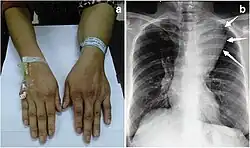

Large mediastinal angiolipoma

Angiolipoma is a subcutaneous nodule with vascular structure, having all other features of a typical lipoma. They are commonly painful.[1]: 624 [2] Angiolipomas manifest as multiple painful subcutaneous nodules commonly on the upper limbs. The can occur sporadically, with a family history or after trauma. Angiolipomas can be seen on CT scans and MRI but are diagnosed based on histopathology. Total excision or liposuction is used to treat angiolipomas. They are more common in men and usually appear in third and second decades of life.

Angiolipoma typically manifests as many, painful subcutaneous nodules (solitary in only one-third of patients), most commonly originating in the upper limbs (of which the forearm accounts for around two thirds), trunk, and lower limbs.[3][4] These lesions are well-defined, usually measuring less than 4 cm.[5]